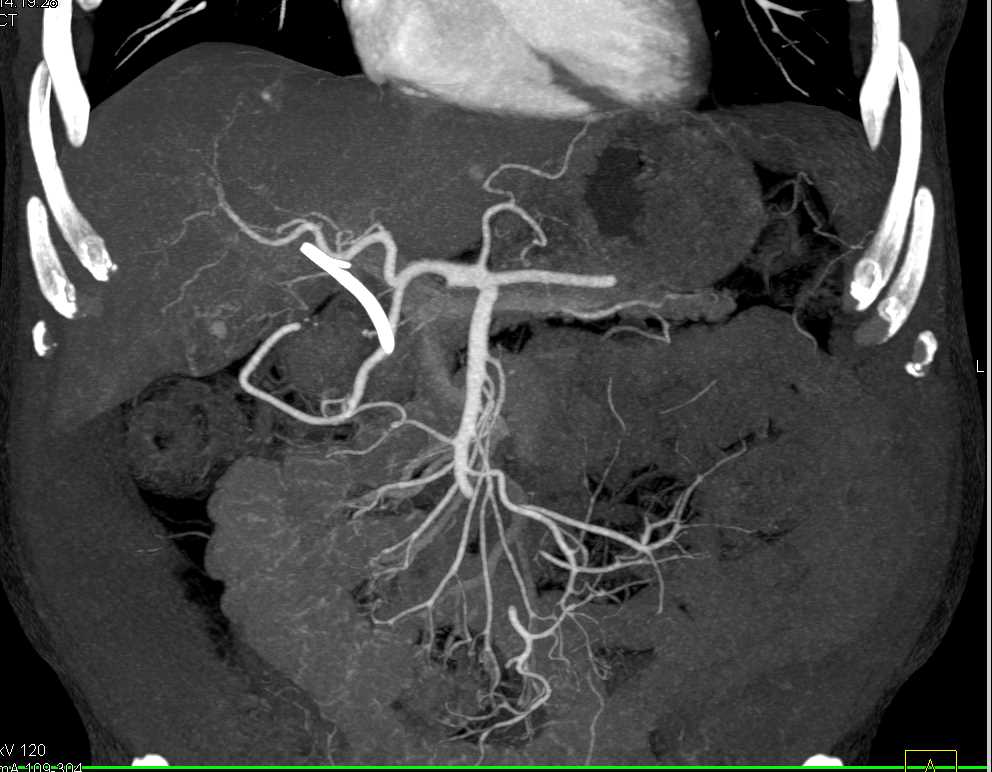

Pancreatic Adenocarcinoma and Incidental Angiomyolipoma (AML) Lower Pole Left Kidney